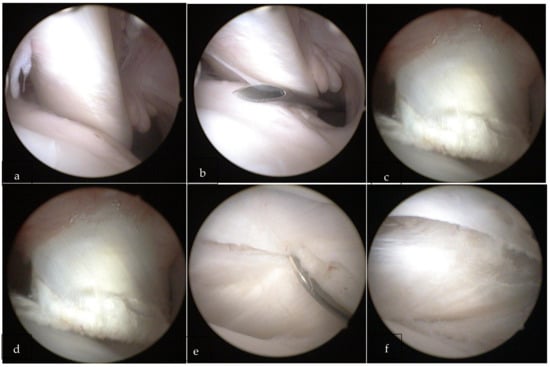

2.2. Surgical Procedure